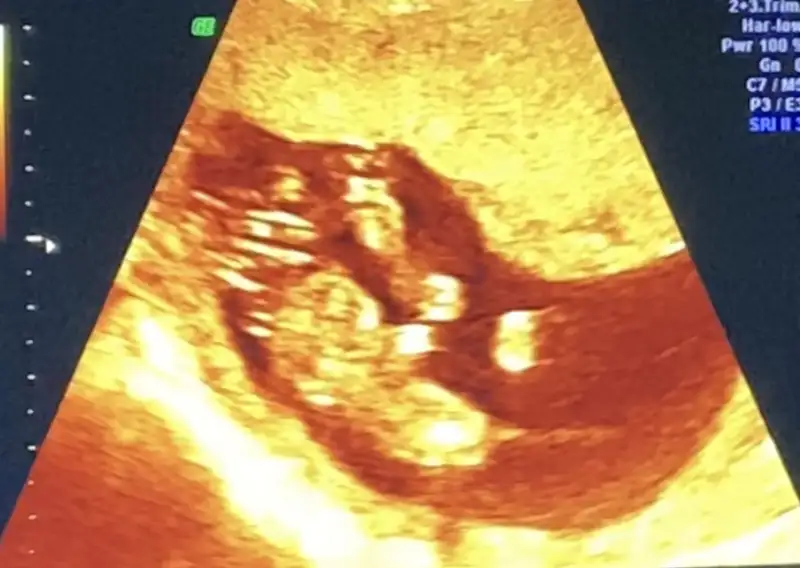

İlk iki foto alttan bakılandan son foto normal daha öncede atmıstım ama cok belli değil demiştiniz bu şekilde bi tahmin olabilirmi Ikra meyra Ikra meyra ☺️

Kızlar sizce cinsiyeti ne lütfen söyleyin sanırım ok'la gösterilen kısım genital bölge